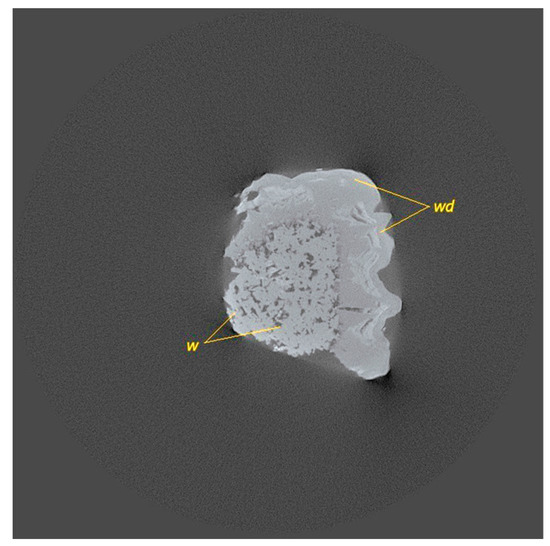

3.1.2. Calcium Phosphate Kidney Stones (F1, F2, F3, M2, M4, and M7)

| F4, F5, F8 | Mixed calcium oxalate (whewellite (w), weddellite (wd), + calcium phosphate hydroxyapatite (a)) | |

| F1, F2, F3, M2, M4, M7 | Mostly calcium phosphate (hydroxyapatite (a) and struvite (s)) + some weddellite (wd) and a very small amount of whewellite (w)) | |